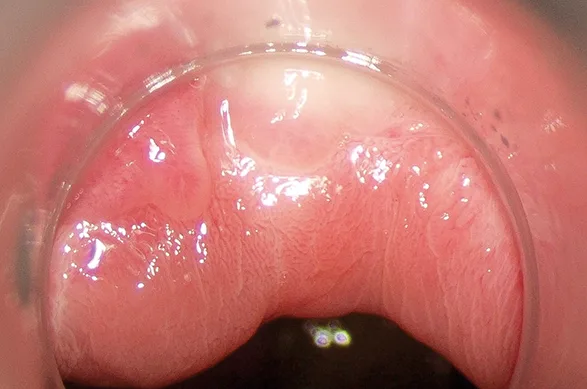

Il s’agit d’un examen de la muqueuse anale sous microscope à faible grossissement à travers un anuscope après application successive d’acide acétique dilué à 3 ou 5 % et de solution de Lugol à 2 %, dans le but de repérer les lésions intra-épithéliales. La combinaison de l’analyse de différents items (aspect, limites, surface, rapidité de la réaction acidophile, anomalies vasculaires et coloration lors de l’application de Lugol…) permet de prédire le grade des anomalies observées et de diriger les biopsies (17-19). Les lésions de haut grade sont volontiers lisses et planes, blanchissent rapidement sous acide acétique, sont associées à des anomalies vasculaires à type de ponctuations et de mosaïques et ont un aspect jaune clair après application de Lugol (photos) (17). Il est essentiel de rechercher des lésions marginales et intracanalaires, notamment en zone transitionnelle. Ces lésions peuvent être multifocales en particulier chez les PVVIH, cette dernière caractéristique étant liée à la persistance des lésions (6). L’examen est plus difficile sur un anus cicatriciel ou radique avec une sémiologie lésionnelle plus difficile à interpréter. L’examen est généralement bien toléré mais peut être vécu comme fastidieux. Enfin, il est parfois impossible en cas de sténose anale ne permettant pas d’introduire un anuscope.

Photo 1 : Aspect de la muqueuse anale en anuscopie et zone transitionnelle

Photo 2 : Séquence de colorations d’une lésion de haut grade en anuscopie de haute résolution (AHR) (A : avant coloration, B : après acide acétique, C : après Lugol)

Photo 3 : Aspect d’une lésion de haut grade avec mosaïques et ponctuations larges

Photo 4 : Aspect d’une lésion de bas grade papillaire avec des vaisseaux tubulisés rigides

Photo 5